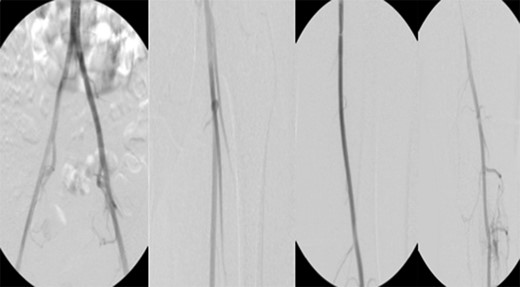

Patient underwent a left lower extremity angiogram. During the procedure she was found to have patent aorta and bilateral common iliac artery. There was no disease visualized in the left external iliac artery, common femoral artery (CFA), SFA, patent previously placed stent, patent above and below the knee PA and two vessel run off to the foot (Fig. 1). Upon delayed fluoroscopic images we identified contrast filling the deep venous system rather quickly suggesting a high volume fistula (Fig. 2). We then identified the fistula between ATA and ATV. Although ATA was previously ligated there was retrograde filling of the artery from unnamed branches, which communicated with the venous system as shown in. In the midcalf (ATA) was cannulated with a micropuncture needle. Micropuncture wire was inserted and a 5-Fr sheath was inserted after exchanging over wire. At this point VortX coils (Boston Scientific) were placed from the curve of ATA until the whole AVF was sealed. Anterograde angiogram showed no flow through the fistula (Figs 3 and 4). There was a palpable PT and DP pulse at the completion of the procedure. Sheath was removed, pressure dressing applied. Patient was discharged home same day. Recovery has been unremarkable. Three months follow-up claudication symptoms have significantly improved.

Fluoroscopy showing; left external iliac artery (EIA), common femoral artery (CFA), superficial femoral artery (SFA), patent previously placed stent, patent above and below the knee popliteal artery (PA) and two vessel run off to the foot.